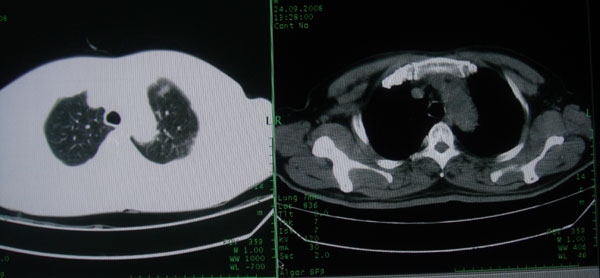

患者男性58岁因二周前起咳嗽,今天胸片示左上肺占位性病变行ct检查,无发热,无咯血痰.

左上肺感染性病变,结核伴空洞形成可能,左上肺膨胀不全

左肺上叶病灶,实变但见含气支气管、空洞但未见壁内结节及积液;

考虑:①感染性病变(包括特殊感染型肺tb)

②肿瘤性病变(考虑患者年龄比较大的关系/所以不排除)

初学者。。。左肺空洞性病变,并可见阻塞性肺不张改变,鉴于患者为老年男性,且临床症状仅有咳嗽,全身中毒症状不明显,所以我首先考虑为左肺癌性空洞并左侧肺门淋巴结转移伴左肺阻塞性肺不张。结核性空洞放于第二位考虑,可以进行相关实验室检查。希望能有病理结果,谢谢!!!!!

左肺上叶实变影,内见支气管充气征及空洞影,病人年龄较大,无发热及结核中毒症状,心影左移,未见纵隔淋巴结肿大;不知实验室检查结果如何?有否嗜酸细胞增多,有没有进行治疗?就目前资料首先考虑1.感染性病变,2.慢性嗜酸性肺炎?可结合实验室检查并短期治疗复查,肺癌不能排除。